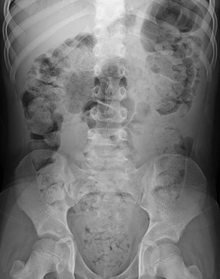

Significant constipation in an 8 year old as seen on plain X ray

The diagnosis is essentially made from the patient's description of the symptoms. Bowel movements that are difficult to pass, very firm, or made up of small hard pellets (like those excreted by rabbits) qualify as constipation, even if they occur every day. Other symptoms related to constipation can include bloating, distension, abdominal pain, headaches, a feeling of fatigue and nervous exhaustion, or a sense of incomplete emptying.[23]

During physical examination, scybala[24] (manually palpable lumps of stool) may be detected on palpation of the abdomen. Rectal examination gives an impression of the anal sphincter tone and whether the lower rectum contains any feces or not. Rectal examination also gives information on the consistency of the stool, the presence of hemorrhoids, admixture of blood and whether any tumors, polyps or abnormalities are present. Physical examination may be done manually by the physician, or by using a colonoscope. X-rays of the abdomen, generally only performed if bowel obstruction is suspected, may reveal extensive impacted fecal matter in the colon, and confirm or rule out other causes of similar symptoms.[7][8]